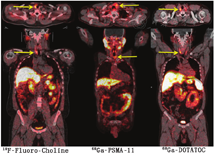

(2)结节性甲状腺肿患者18F-FDG PET/CT检查。在所有18F-FDG显像中,有1%~2%的偶发瘤——在因与甲状腺无关的原因行18F-FDG PET/CT显像时(通常在非甲状腺癌患者中)被发现甲状腺显像剂摄取增加。观察到2种18F-FDG摄取模式,分别为弥漫性和局灶性(图4)。甲状腺弥漫性摄取18F-FDG通常与自身免疫性甲状腺炎有关,几乎没有临床意义[30,31,32]。甲状腺局灶性摄取18F-FDG可见于结节性甲状腺肿,这些偶然发现的结节中约有35%是甲状腺癌[33]。因此,对这些病例应行进一步的检查,以明确结节的性质[34]。在PET/CT显像中意外发现甲状腺肿瘤并不是只有18F-FDG能做到,通过其他的PET肿瘤显像剂也能观察到,例如18F-氟胆碱、68Ga- 1,4,7,10-四氮杂环十二烷-1,4,7,10-四乙酸-苯丙氨酸1-酪氨酸3-奥曲肽(1,4,7,10-tetraazacyclododecane-1,4,7,10-tetraacetic acid(D)-Phe 1-Tyr3-octreotide, DOTATOC)和68Ga-前列腺特异膜抗原配体(图5)[35,36,37]。